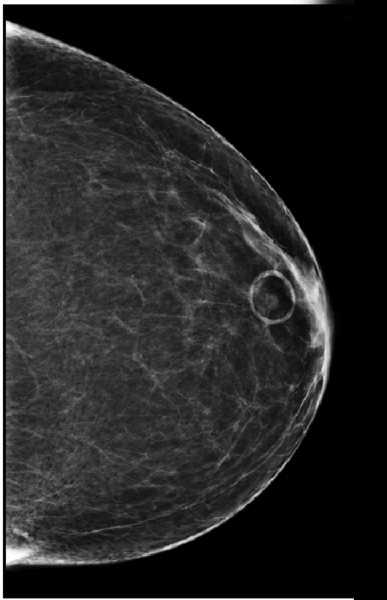

To further emphasize how mole markers clarify findings and improve interpretation, Figure 2 shows a L CC view with a circular marker denoting a skin mole. Figure 3 shows the corresponding MLO view. The retroareolar asymmetry on the CC view would not be as obvious as corresponding to the skin lesion on the MLO view without the mole marker.

“If the mole marker had not been used,” Jacobs explained, “this patient would have been called back for additional views. Having the skin marker lets you correlate with 100 percent certainty that it is the same finding on the two views.”